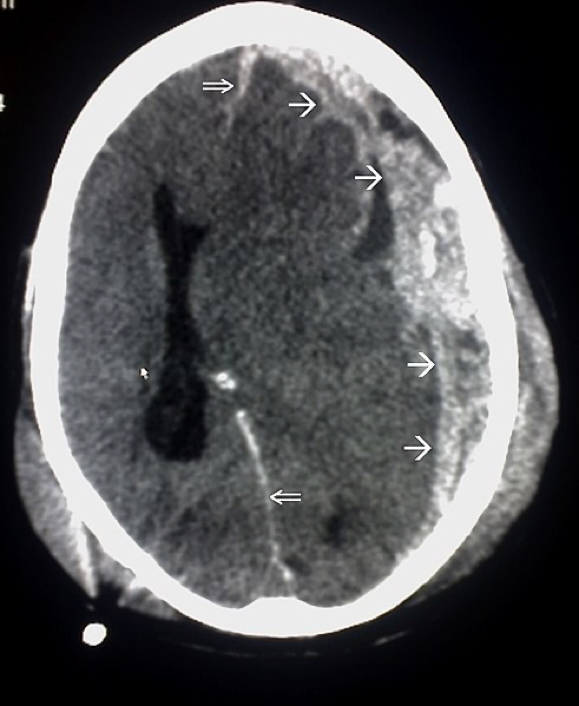

Intracerebral Haemorrhage

- Bleeding into brain parenchyma

- Leads to mass effect, ↑ICP, and ischaemia

Morphology

- Slit haemorrhages in chronic HTN

- Lacunar infarcts in brainstem/basal ganglia

Investigations

- CT/MRI Brain: Confirms haemorrhage